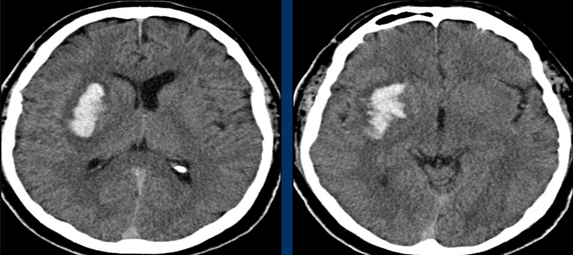

Cho thấy tắc nghẽn, hẹp mạch máu cũng như tình tràng tuần hoàn nối, bàng hệ.

Hình ảnh tắc động mạch não giữa MCA bên phải trên CTA